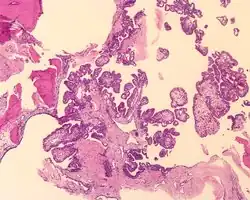

The microscopic appearance shows an unencapsulated, destructive growth, remodeling and invading bone. The tumor is arranged as simple, broad, non-complex papillary projections without large cystic spaces. The spaces are often fluid filled, have extravasated erythrocytes and/or inspissated material. The cells are cuboidal, usually single layered along the papillary structures, showing indistinct cell borders. The nuclei are round and hyperchromatic.[1][3][10][11]